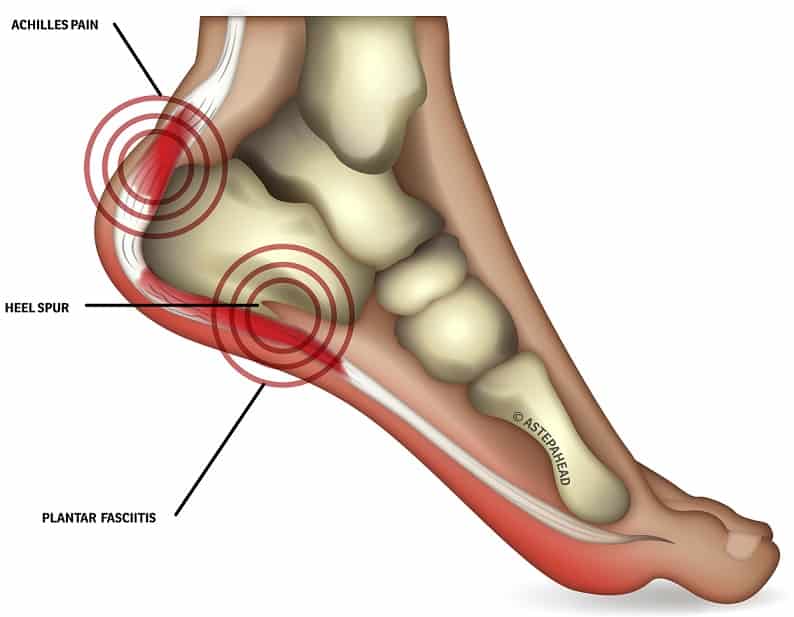

Heel Pain Causes and Treatment clearance, Heel Pain Causes Diagnosis Treatment clearance, Foot Pain Causes Treatment clearance, Plantar fasciitis treatment symptoms and causes healthdirect clearance, Plantar fasciitis Symptoms and causes Mayo Clinic clearance, Heel Pain Plantar Fasciitis is a common and Painful Condition clearance, Plantar Fasciitis Causes Symptoms Treatments and More clearance, Heel Pain causes and treatment plantar fasciitis diagnosis and treatment clearance, All About Heel Spurs Causes Treatments and Prevention Westfield Foot and Ankle LLC clearance, Plantar Fasciitis Symptoms Causes Treatment Options clearance, Plantar Fasciitis The Literal Pain In Your Heel Orthopaedic Associates of Duluth clearance, Pain in the Back of the Heel Causes and Treatment clearance, Heel Pain Types Symptoms Causes and Treatment clearance, Heel Pain Plantar Fasciitis Complete Physio clearance, Causes of Heel Pain clearance, Patient Basics Heel Pain 2 Minute Medicine clearance, Heel Pain 4 Major Causes and how to prevent them clearance, That Pain in Your Feet May be Plantar Fasciitis clearance, Heel Pain A Step Ahead Foot and Ankle Care clearance, Suffering With Plantar Fasciitis Heel Pain Symptoms Treatment clearance, Heel Pain Treatment Foot Doctor Toronto Ontario M3H 3S3 clearance, Pinpoint Your Foot Ankle Pain OrthoNebraska clearance, Heel Fat Pad Syndrome Symptoms Causes Treatment clearance, Heel Pain Podiatrist In Sterling Heights MI Advanced Foot Ankle Wound Care clearance, Plantar Fasciitis Treatment Symptoms Causes Prevention PediFix clearance, What s Causing My Heel Pain Quick Pain Relief Performance Health clearance, Why does top my heel hurt clearance, Heel Pain Treatment Nassau County Podiatrist clearance, Plantar fasciitis Information Mount Sinai New York clearance, Causes of Heel Pain clearance, Plantar Fasciitis and Foot Pain clearance, 4 Exercises to Relieve Heel Pain Kelly L. Geoghan DPM Podiatrist clearance, Why Does My Heel Hurt Syracuse Podiatry Dr. Ryan D Amico clearance, Dealing With Foot Problems Lucky Feet Shoes Has Hundreds of Styles to Help Ease Your Foot Pain clearance, Heel Spurs Causes Solutions Diagnostic Foot Specialists clearance.